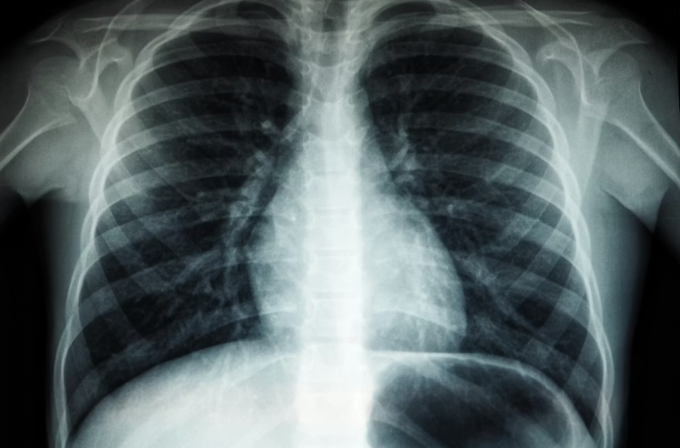

결핵 진단을 위해서는 몸속에 결핵균이 있는지 확인해야 한다. 폐결핵은 보통 가래를 이용해 항산균 도말 검사, 항산균 배양 검사, 결핵균 유전자 검사를 기본으로 시행한다. 흉부 엑스레이, 흉부 전산화단층촬영(CT) 등도 폐결핵의 진단과 치료 경과를 확인하는 데 이용된다.